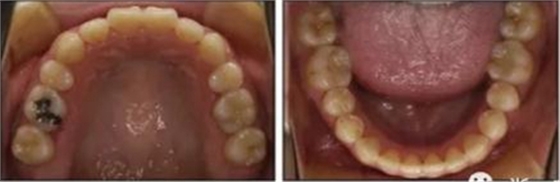

治療后數(shù)據(jù)提示治療目標(biāo)達(dá)成。面相結(jié)果提示微笑及側(cè)貌得到改善(圖6)。達(dá)到了安氏I類尖牙關(guān)系和安氏II類磨牙關(guān)系,形成尖牙保護(hù)合。牙齒中線無偏斜,達(dá)到理想的覆合覆蓋,Spee曲線得到整平。

治療后全景片提示間隙得到關(guān)閉,除了左下頜第一前磨牙外牙根平行度可,無明顯骨及牙根吸收。(圖7)